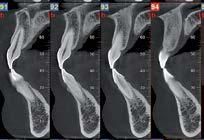

Nell’ambito della radiologia 3D ortopedica, il centro diagnostico utilizza il nuovissimo macchinario NewTom 5G XL, in grado di individuare con la massima precisione la presenza di fratture o lussazioni delle articolazioni, controllare la corretta guarigione di una frattura, valutare una lesione o una ferita causata da infezione, artrite o crescita anormale dell’osso.

Il tutto mediante una semplice e veloce scansione, grazie alla quale si otterranno diverse immagini in 3D ad altissima risoluzione e, per ottenere immagini ancora più nitide mediante un bassissimo dosaggio di radiazioni, gli esperti si avvalgono dell’innovazione racchiusa nella tecnologia Cone Beam.

Se con la radiologia tradizionale era necessario eseguire scansioni multiple, la novità introdotta dal macchinario NewTom 5G XL risiede nella capacità di fornire immagini ad alta risoluzione in un’unica scansione, mostrando nitidamente i dettagli delle articolazioni degli arti superiori e inferiori. Inoltre, a differenza della tecnologia 2D, la radiologia 3D ortopedica permette di individuare immediatamente alcune patologie come quella del metatarso, la quale richiede un allineamento visivo dedicato o una diagnosi delle micro fratture ossee.